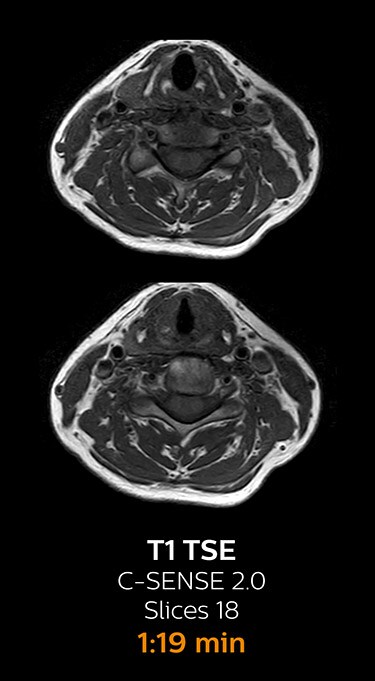

Clinical example: Fast MRI of cervical spine

With Compressed SENSE, the scan time for the routine cervical spine examination at KNC was reduced from 13:11 to 9:52 minutes, which corresponds to 25% reduction.

MRI of cervical spine with Compressed SENSE